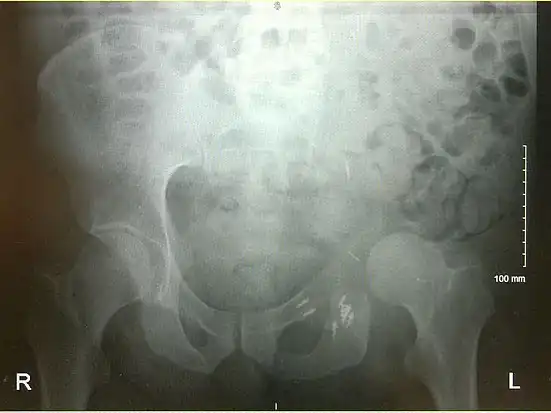

An x-ray of a limb-sparing hemipelvectomy on the left side of a male pelvis taken one month after surgery.

An x-ray of the same pelvis taken eighteen months after surgery highlighting the femur migration to its final resting place.